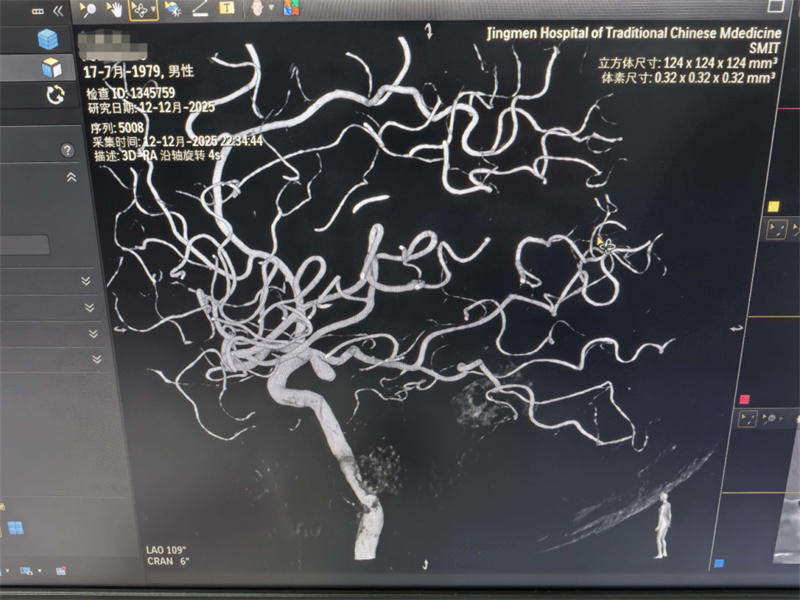

近日,荆门市中医医院上演了一场与死神赛跑的紧急救治,依托多学科协作(MDT)模式,医院各科室高效联动,成功为一名突发“左侧大脑后动脉瘤破裂并蛛网膜下腔出血”的患者实施介入栓塞手术。目前,患者在ICU接受进一步监护治疗,病情已趋于稳定。

患者紧急转运至医院后,神经外科与神经内科医护团队即刻启动联合会诊机制,医院同步开放急救绿色通道,为患者加急完成脑部CT及CTA检查,快速明确 “左侧大脑后动脉瘤破裂并蛛网膜下腔出血” 的诊断。考虑到患者家属远在浙江异地,医护人员主动加急联系家属,详细告知病情进展与初步救治计划,缓解家属担忧。

为最大程度降低手术风险,医院组织全院多学科会诊,神经外科,麻醉科、放射科、介入导管室等科室专家齐聚一堂,与特邀的中南医院冯教授共同研讨,结合患者病情制定了周密的介入栓塞手术方案。

在全麻状态下,神经外科手术团队默契配合,凭借精湛的技术顺利完成脑动脉瘤介入栓塞手术,成功封堵破裂血管,有效控制出血,挽救病人的生命。此次手术的圆满成功,不仅体现了荆门市中医医院急危重症救治的快速响应能力,更彰显了多学科协作模式在复杂病例救治中的重要价值。